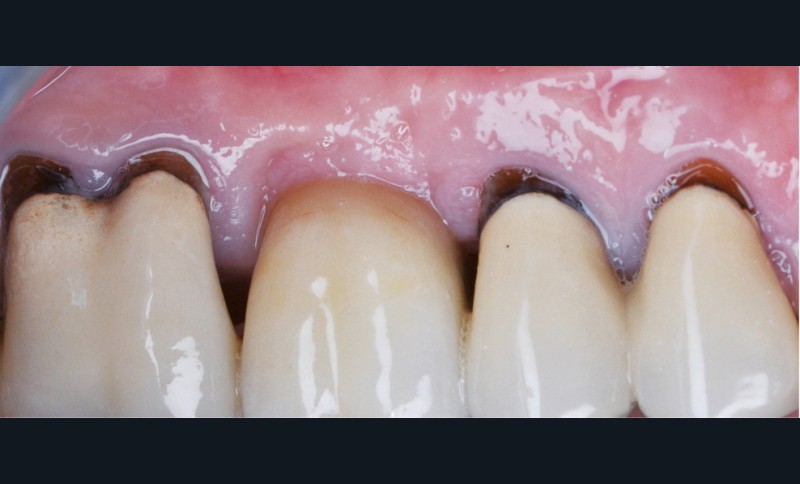

Zuchelli et coll. [1] définissent quatre causes à l’origine des récessions gingivales à la suite d’une déhiscence osseuse : les causes traumatiques (fig. 1) par le brossage, le surcontour prothétique, les piercings ; les causes bactériennes (fig. 2) liées à une inflammation marginale ; les causes virales par le virus de l’herpès simple ; et les origines mixtes, à savoir traumatiques et bactériennes (fig. 3). Le diagnostic de récession liée à la plaque dentaire dépend de la présence de dépôts tartriques et/ou d’inflammation des tissus environnant les zones exposées. En présence d’une origine mixte, la récession est d’abord initiée par un brossage traumatisant, rendant la surface radiculaire hypersensible ou irrégulière, ayant une répercussion négative sur le brossage et l’accessibilité à l’hygiène.